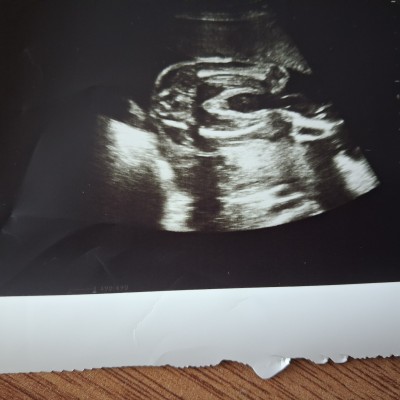

Cinsiyet tahmini yapabilenlerden ricam yorumlayabilir mi 25 haftaligim

Gebelik haftası 25. Hafta

Kız bu bildiğin erkek 😀 bide 25 haftaya kadar hiç mi bişey demedi doktor

Önce erkek dedi simdide emin olamadım dedı benim ikiz gebelik birini kesin kız dedi bunda emin olamıyor

Gördüğüm kordon değilse erkek gibi ama bilemiyorum yinede

Ekek deyilki kiz bu

Benimde 15ve 16 haftalık iken pipisini gösterdi doktor kesin erkek dedi sonrası hep kız dediler detaylı ultrasonda da aynı bu şekilde bu görüntüde kız dedi hatta diyecektim kız ise neden öyle orası şiş gibi sonra sormadım acaba benimde erkekmi doğumda sürpriz mi olacak 35+3 şuan çok isterim öyle güzel bir sürpriz olsun ikide kızım var Rabbim herkesin gönlüne göre versin inşallah

Erkek bêncê canım